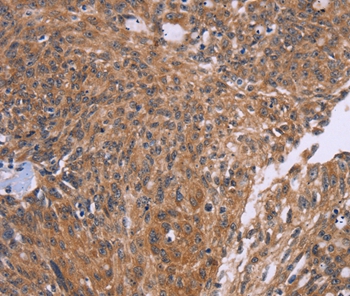

Immunohistochemical analysis of paraffin-embedded Human thyroid cancer tissue using #36378 at dilution 1/50.

Immunohistochemical analysis of paraffin-embedded Human ovarain cancer tissue using #36378 at dilution 1/50.